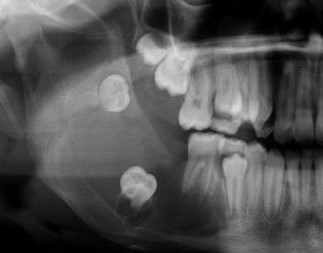

@theBSOMP Case of the Month for Jan/Feb 2024 is now live.

Visit bsomp.org.uk/cotm for details.

Case credit-@histopathhannah @M0llieclark